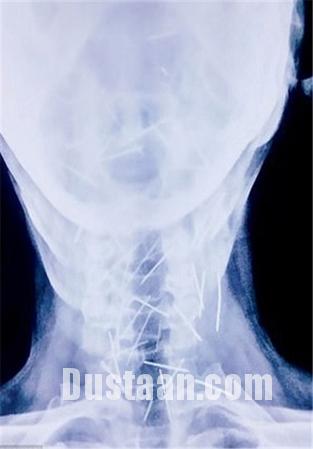

پزشکان با مراجعه مردی جوان به بیمارستان که عنوان داشت در ناحیه گلو و کف پایش احساس درد دارد، اقدام به عکسبرداری از وی کردند، انها در کمال تعجب مشاهده کردند که بیش از ۷۵ سوزن در گلو و دیگر بخش های بدن او فرو رفته است!

«بادریلال مینا» که از اهالی ایالت راجستان است، از وجود این سوزن ها اظهار بی اطلاعی می کند! اما حقیقت چیز دیگریست چرا که فرو رفتن این سوزن ها در بدن وی قطعا بدون درد نبوده و وی از وجود سوزن ها مطلع بوده است.